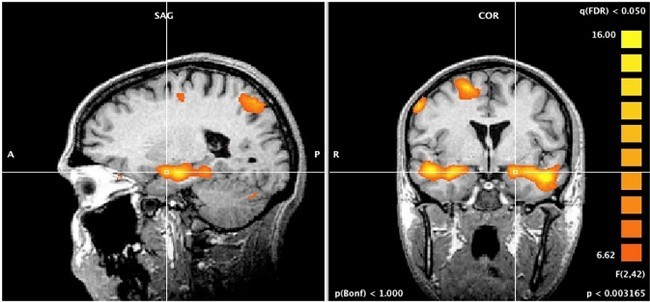

Brain changes with cognitive behavioral therapy